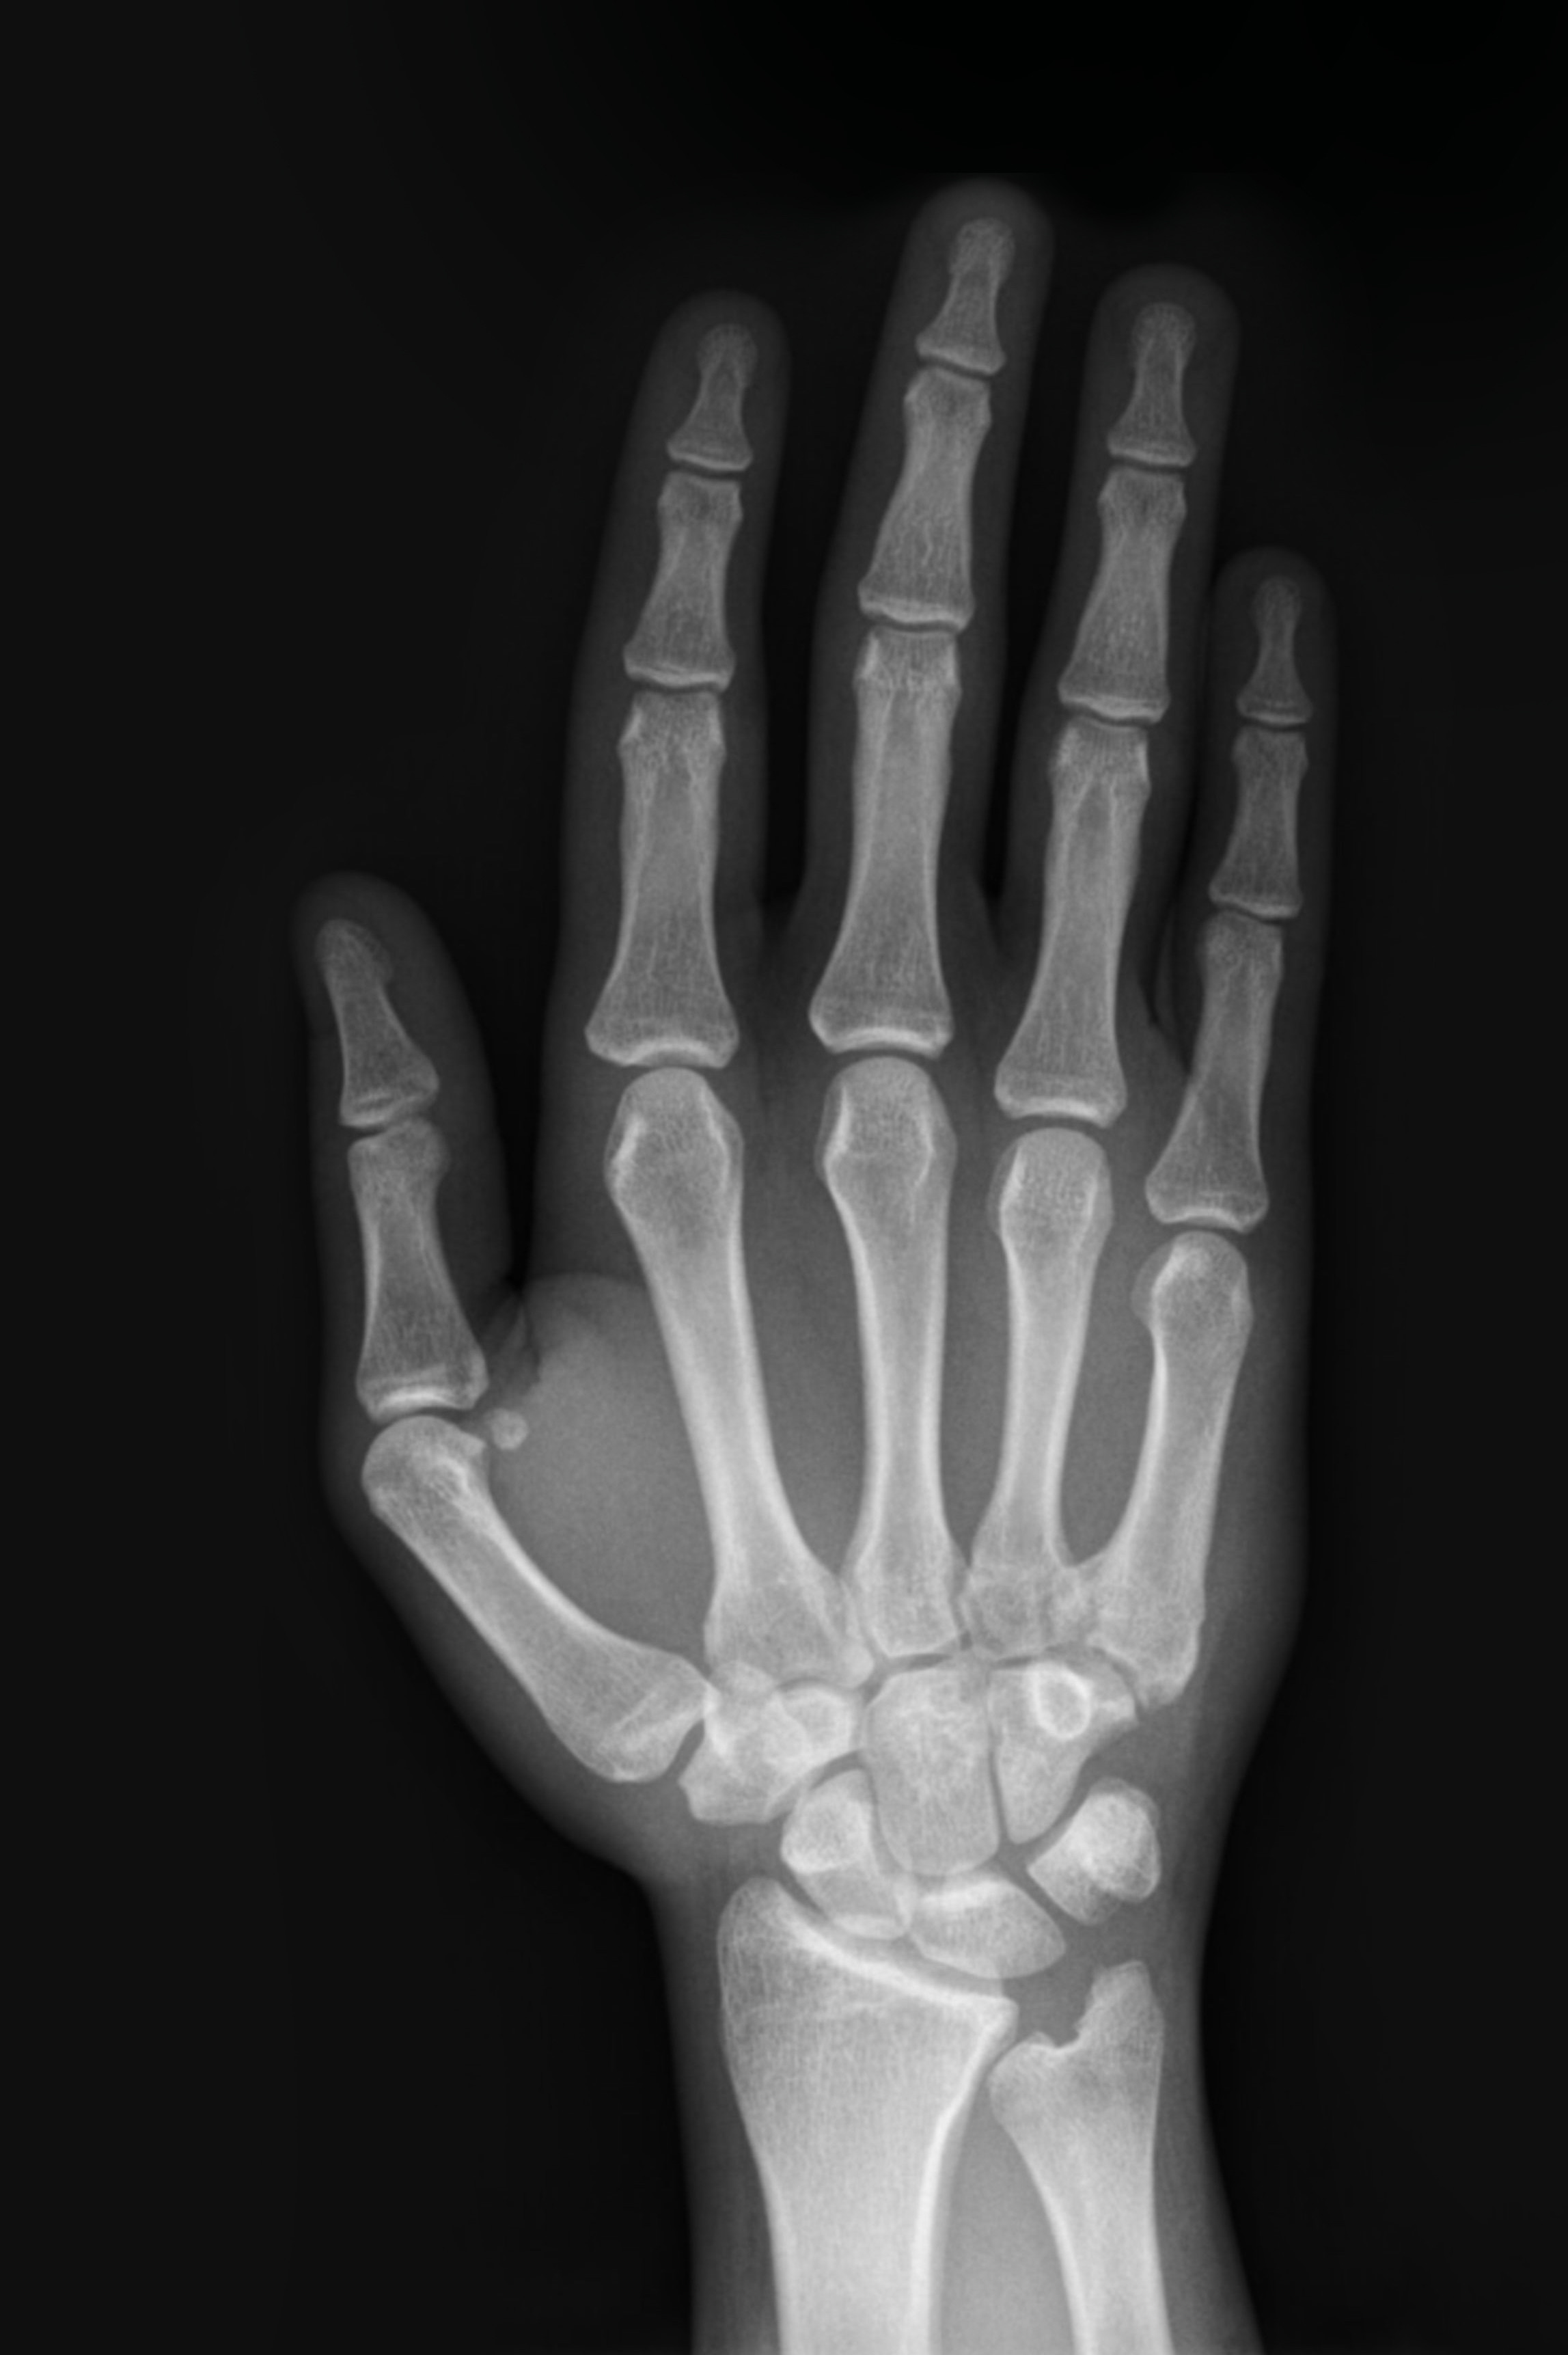

Strikte Beachtung der Indikationsstellung.

Ist diese nichtvollumfänglich gegeben, ist von

Handröntgenaufnahmen Abstand zu nehmen.

© Dr. Georg Bach

4. Handaufnahme/Handröntgen

Die aktuelle skelettale Wachstumsphase einer/eines jungen Patient/-in kann durch die Analyse der Handentwicklung ermittelt werden. Von dieser Wachstumsaktivität sind wiederum wesentliche Behandlungsschritte wie ­die Korrektur der Unterkieferlage oder die Bisshebung maßgeblich abhängig. Handröntgenaufnahmen werden in der Zahnmedizin somit überwiegend von Kieferorthopäden genutzt, die diese Aufnahmetechnik als „biolo­gische Uhr“ betrachten. Dennoch gehört die Handröntgenaufnahme nicht zur KFO-Routinediagnostik. Deren Einsatz bedingt eine strenge Indikationsstellung und eine entsprechende diagnostische Fragestellung:

• wenn im Rahmen einer KFO-Behandlung Wachstum zur Bisslagenkorrektur oder Bisshebung ausgenutzt werden soll

• wenn während oder nach einer kieferorthopädischen Therapie negative wachstumsbedingte Folgen befürchtet werden und eine Beurteilung des Restwachstums erfolgen muss

• wenn eine deutliche Abweichung zwischen chronologischem und dentalem Alter vorliegt

• bei Planung der forcierten Gaumennahterweiterung

• bei interdisziplinär (KFO-Chirurgie) geführten Behandlungsfällen

• wenn ein operativer Eingriff bei ausgeprägten skelettalen Dysgnathien zwischen dem 16. und 20. Lebensjahr erfolgen soll.

Die Auswertung der Handröntgenaufnahme erfolgt nach einem fest­gelegten Schema. Die Beurteilung wird anhand des Größenverhältnisses Diaphyse zu Epiphyse vorgenommen. Die Definition von Reife- und Entwicklungsfaktoren, die regelmäßig in einer bestimmten Reihenfolge während der Skelettentwicklung auftreten, ermöglicht die diagnostische Auswertung der Aufnahme und die daraus resultierenden therapeutischen Entscheidungen.